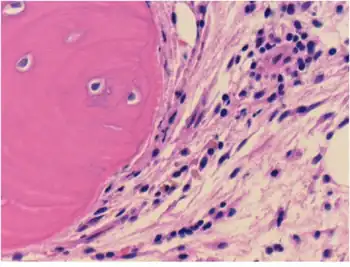

Connective tissue with mild infiltration by mononuclear inflammatory cells